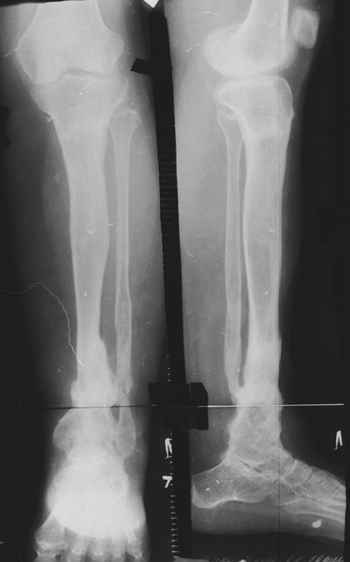

На первом этапе аппаратом Илизарова закрыто устранена деформация голени.

На втором этапе произведёно освежение краёв костных фрагментов б/б и м/б костей с приданием проксимальному фрагменту б/б кости впалой, а дистальному выпуклой формы, открытие канала проксимального фрагмента и погружной остеосинтез, а также остеотомия б/б кости в в/3 и м/б кости на границе с/3 и н/3 голени. Больной проводился одновременный бифокальный компрессионно-дистракционный остеосинтез. Достигнуто 11 см. удлинение и сращение ВПГ.

Срок лечения 11 месяцев. Наблюдение 2 года.